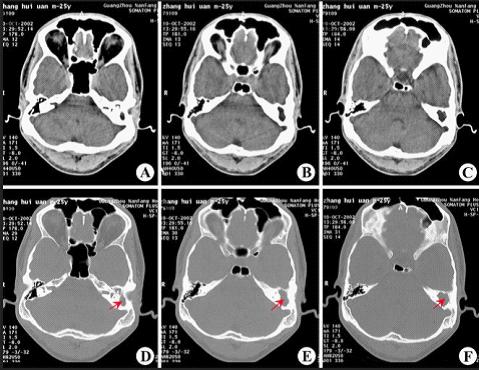

CT显示:左侧慢性中耳乳突炎(胆脂瘤型)